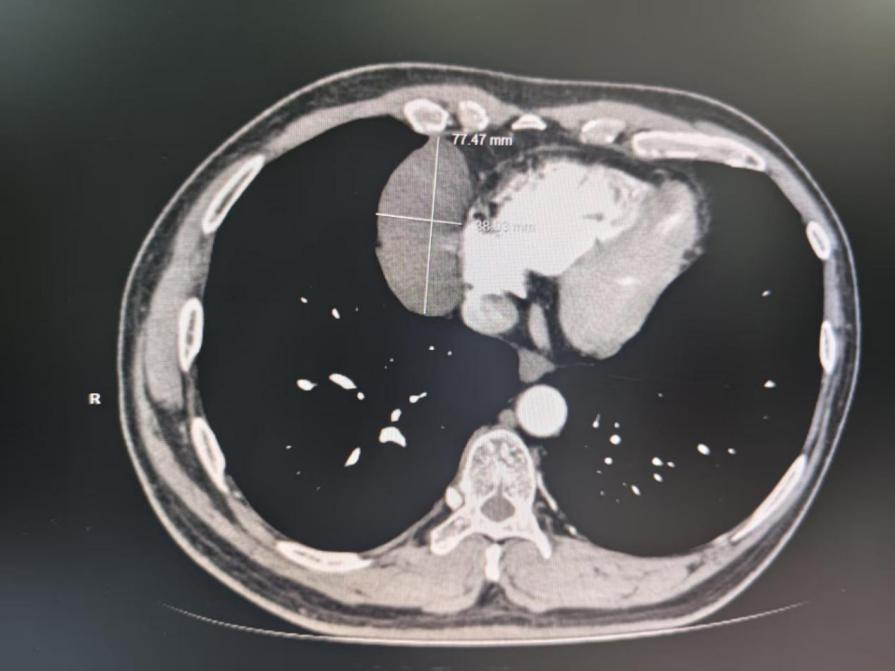

44歲的文先生,在活動后常常出現胸前悶脹不適的癥狀。經過詳細檢查,發現其體內存在一個直徑約8cm的巨大右前縱隔腫物,且該腫物緊緊貼附在心臟表面,使得手術難度大幅增加,風險極高。若采用傳統的開胸手術,患者將面臨較大創傷、漫長恢復時間以及心肺功能受到較大影響的困境。

患者縱隔腫物影像。通訊員供圖